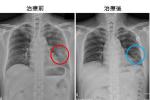

臺南市立安南醫院胸腔內科林延淞醫師表示,晚期肺癌治療屬於「個人化治療」,主要治療目標,是希望改善病人生活品質,延長存活率,目前的治療方式可採取化學治療標靶治療及放射治療來延緩病情,一般而言約有7成左右的療效,是肺癌末期病人的新曙光。

胸腔科醫療團隊施予標靶、化療放射線等「個人化」肺癌治療方式,採對病人最合適及有效的組合治療,3位病人均得以延長好幾年的生命餘期,也保障其生活品質,並爭取到更多與親友相伴的日子

林延淞說,肺癌主要可分爲小細胞肺癌(13~15%)及非小細胞肺癌(80~85%)、鱗狀上皮癌、腺癌、大細胞肺癌等。醫學上肺癌的治療方式主要有手術治療、化學治療、放射線治療及標靶治療。至於臨牀上治療,醫師究竟要如何取決哪一種方式,端視病人肺癌的類型(是非小細胞亦或是小細胞肺癌)以及腫瘤的大小、位置與嚴重程度和病人的健康狀況如何。